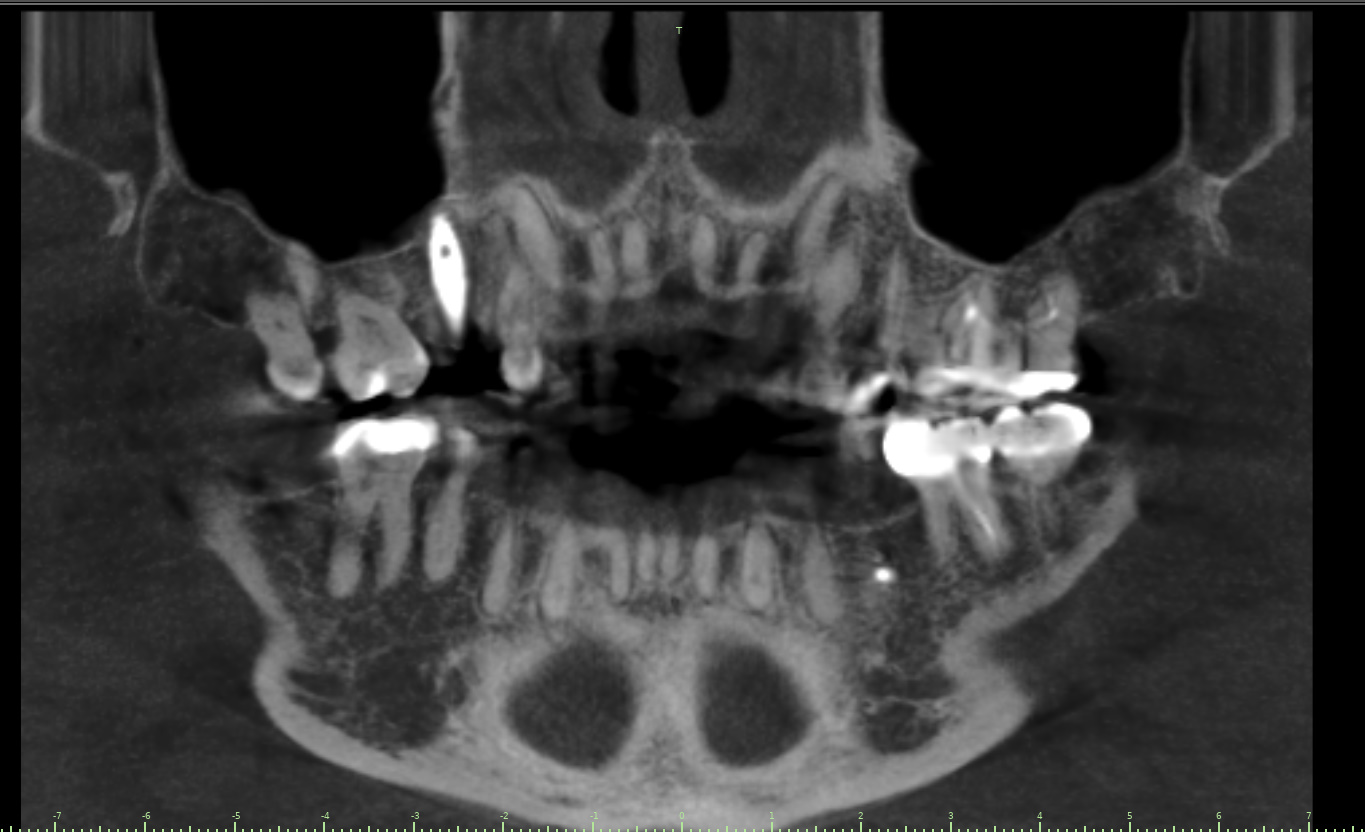

Surgical program case from Dental Implant Institute